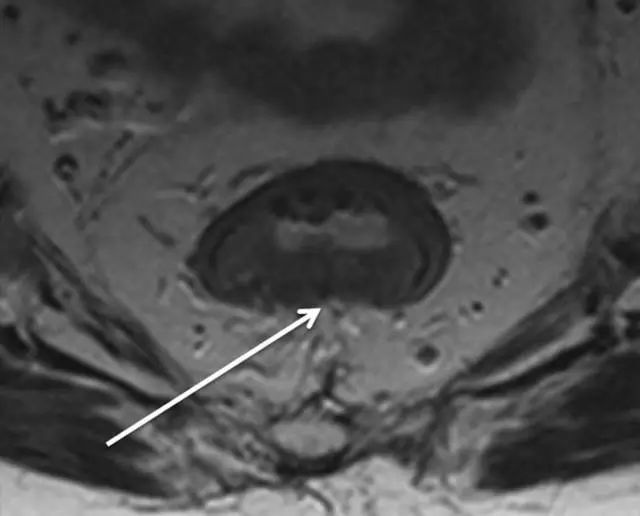

图片

62 岁直肠癌妇女,薄层 T2 加权轴位 MR 图像显示直肠癌,在 9 点钟位置。

箭头显示直肠系膜筋膜。